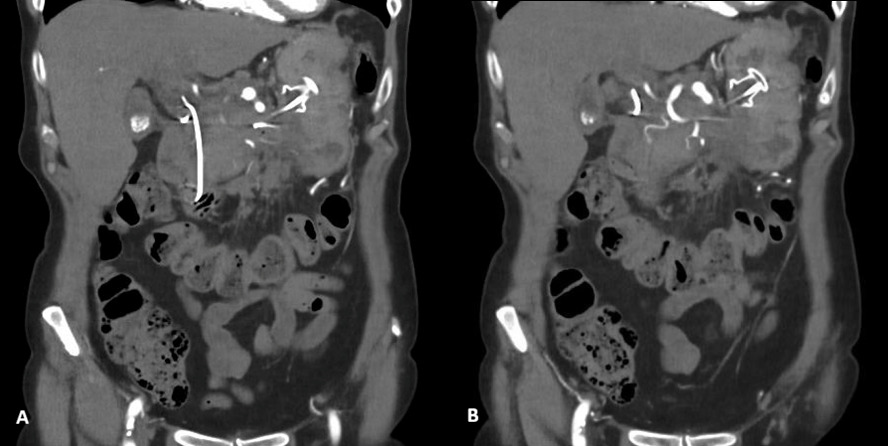

Further evaluation with Doppler ultrasound demonstrated non-occlusive bland thrombus within the common hepatic and left hepatic arteries. A subsequent CT angiogram (CTA), performed four weeks after the initial CT, confirmed the presence of multiple visceral pseudoaneurysms involving the hepatic arterial system. These included aneurysms of the right hepatic artery measuring 5.5 mm and 5.8 mm, intermediate hepatic artery aneurysms measuring 7.7 mm, 5.7 mm, and 14 mm, and a left hepatic artery aneurysm measuring 10.4 mm. Additionally, the coeliac trunk appeared diffusely aneurysmal with associated luminal irregularity (figure 3). All aneurysms demonstrated interval enlargement compared with prior imaging (Figure 2). Notably, during this period, the patient’s inflammatory markers and liver function tests had normalised.